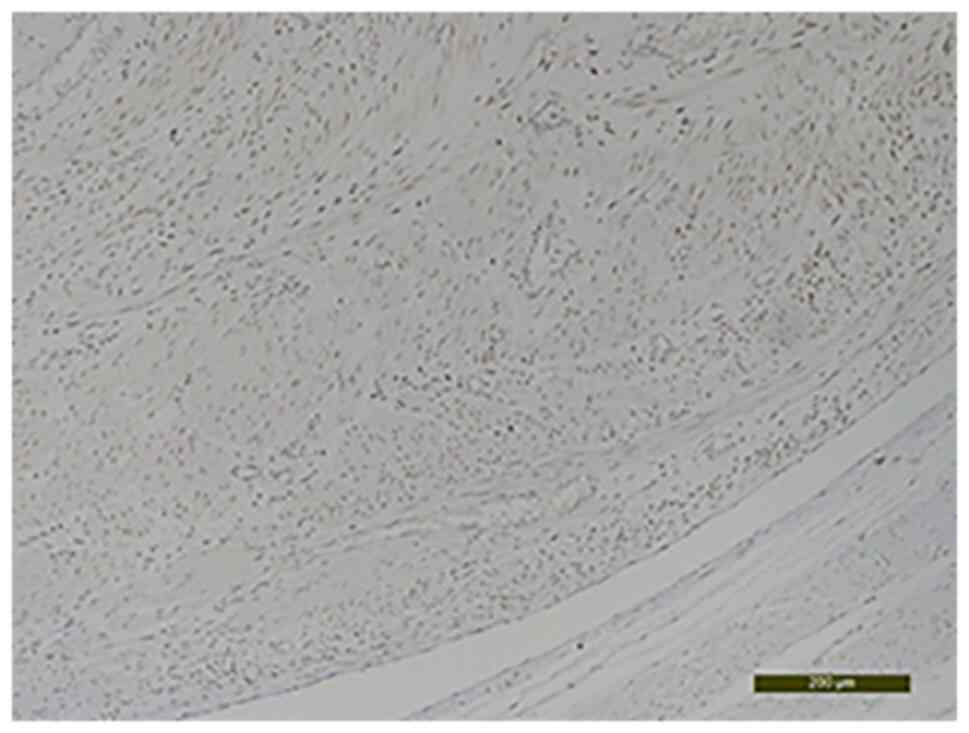

The histological examination with hematoxylin-eosin staining showed fusiform cells that had moderate nuclear atypia, rare mitosis, areas of sclerosis and hyalinosis, interstitial edema and degenerative modifications. The specimen was processed according to standard histological technique and the slides were stained with the conventional hematoxylin and eosin staining (HE) method (7). Briefly, the uterine mass tissues was fixed in formaldehyde (neutral buffered formalin 10%) for 24 h at room temperature (24˚C) and then the specimen was dehydrated in alcohol, cleared in xylene and embedded in paraffin. Clarification was achieved by passing the fragments through three xylene baths to remove alcohol from the tissues, for 4-6 h. The impregnation with paraffin was achieved by placing the tissue fragments in three paraffin baths for a minimum of 24 h at a temperature of 56˚C. The slides obtained were placed in a thermostat at 58˚C for 24 h and later stained using HE staining. The paraffin blocks were sectioned at 4 µm. The tumor with intravascular growth featured uniform spindle-shaped smooth muscle cells (Fig. 5, Fig. 6 and Fig. 7). Also, the presence of adenomyosis was confirmed. This diagnosis was not suspected prior to the surgery and it was an unusual histopathological finding.

Figure 5

Interlacing bundles of smooth muscle cells arranged in an anastomosing fascicular pattern (hematoxylin-eosin staining; magnification, x10).